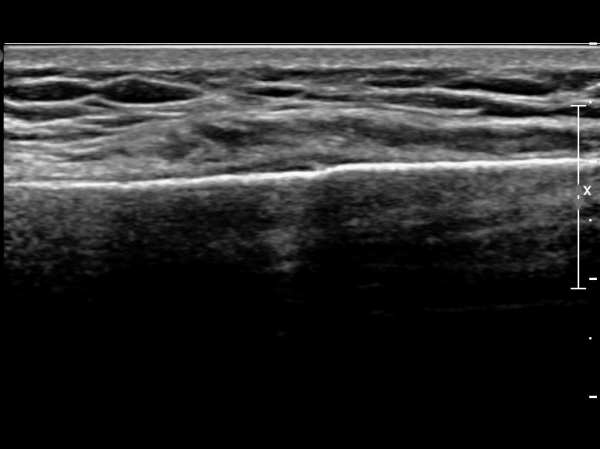

Äá¾Ë»À Á¾´Ü¸é°Ë»ç¿¡¼­ Äá¾Ë »À ±ÙÀ§ºÎÀÇ ÇÇÁú°ñ °ß¿­ÀÌ °üÂûµÊ(»çÁö 4).